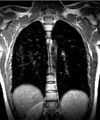

Последние исследования ученых показывают, что одной из причин развития рака легких являются вирусы.

Эксперты утверждают, что курение является самым отдаленным фактором, который может стать причиной рака легких.

При проведении исследований над пациентами, которые страдали от рака легких, выяснилось, что большой процент среди них переболели такими вирусами, как вирус папилломы, корь, стали причиной рака легких.